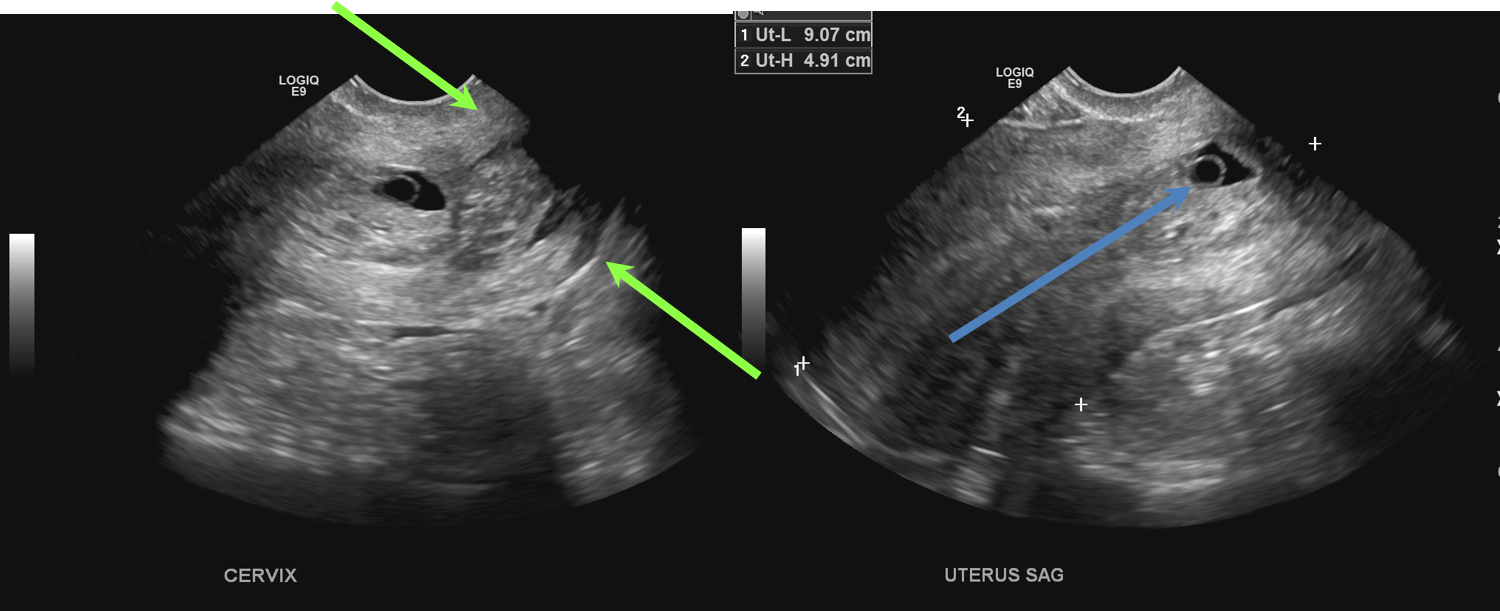

- A gestational sac and a yolk sac (blue arrow) are seen in the endocervical canal. There are blood products in the canal. The cervix is open (green arrows).